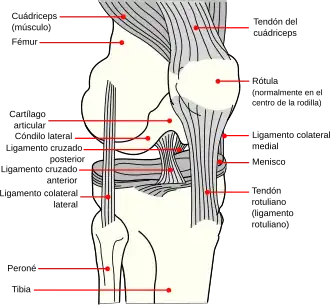

La rótula[1] (patella) es un hueso sesamoideo situado en el plano anterior de la articulación de la rodilla, engastada en el tendón del cuádriceps. Es aplanada, de forma triangular con vértice inferior, y su eje mayor mide unos 5 cm. El borde superior (base) y la cara anterior reciben las fibras del tendón del cuádriceps, y de su vértice parte el ligamento rotuliano que continúa al tendón del cuádriceps. La cara posterior (cara articular) posee la superficie articular para el fémur y, por debajo, una zona rugosa relacionada con formaciones adiposas de la articulación de la rodilla. La superficie articular consta de dos vertientes laterales separadas por una cresta roma central que se adaptan a la superficie rotuliana del fémur. Se considera el hueso sesamoideo más grande del cuerpo humano.

Se encuentra en la parte anterior de la rodilla. Su vértice se articula con el fémur. La rótula es un hueso plano y redondeado que se encuentra incluido en el tendón terminal del músculo cuadriceps femoral y está situado por delante de la extremidad inferior del fémur.

Las cuatro cabezas del cuádriceps (M. vasto intermedio, M. vasto lateral, M. vasto medial, M. recto femoral) se condensan en láminas tendinosas que confluyen en la proximidad de la rótula formando el tendón del cuádriceps, en cuyo espesor se localiza la rótula. El mayor componente de fibras emerge por el vértice inferior de la rótula y forma una potente cinta tendinosa denominada ligamento rotuliano que se inserta en la tuberosidad de la tibia.

Del sector inferior de los bordes laterales de la rótula emergen láminas fibrosas, las cuales contribuyen a reforzar la articulación de la rodilla. Un aspecto de interés es que los componentes tendinosos fibrilares de cada vientre del cuádriceps ocupan planos diferentes y pueden ser identificados en la región rotuliana. Las fibras del recto femoral, son las más superficiales y algunas de ellas saltan hasta el ligamento rotuliano sin insertarse en la rótula. Las fibras de los vasto medial y vasto lateral y ocupan un plano más profundo y, como se ha descrito antes, parte de sus componentes emergen por los bordes laterales de la rótula para reforzar la articulación de la rodilla. Las fibras más profundas son las del vasto intermedio, que se agotan en el borde superior de la rótula. Por encima de la rótula puede aparecer una bolsa sinovial interpuesta entre los planos tendinosos superficial y profundo del tendón del cuádriceps (bolsa subtendinosa prerrotuliana).